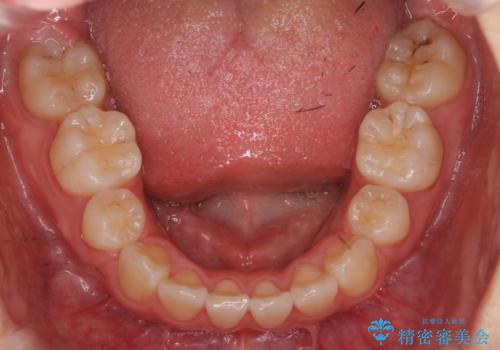

成人式の1年前から矯正をはじめ、成人式前に上の前歯の装置を一時的にとりました。

一時的に装置を取ることで、多少治療期間が伸びましたが、それでも、2年かからずに外すことができました。

成人式の時に前歯が下がって、揃った状態で写真を撮ることができ、大変喜んでおられました。